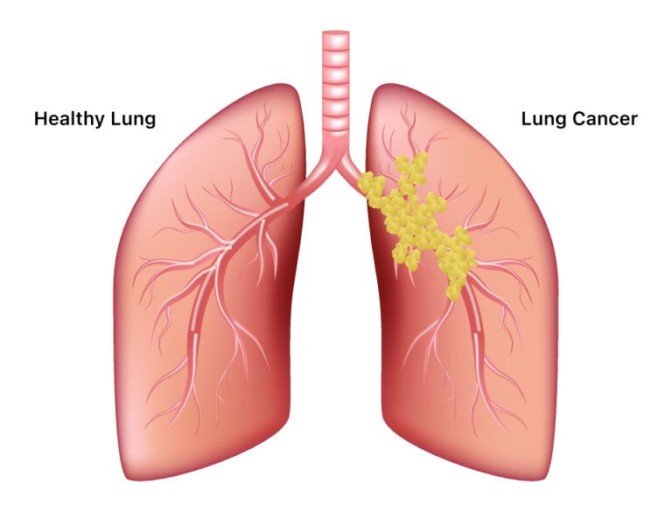

오늘은 우리 몸의 호흡을 책임지는 폐에 대해 이야기하려 합니다. 특히, 폐에 발생하는 악성 종양인 폐암의 초기 증상에 대해 자세히 알아보려 합니다.

폐암 초기증상 폐암은 초기 증상이 감기나 다른 호흡기 질환과 비슷해 간과하기 쉽습니다. 하지만 조기 발견이 치료에 매우 중요하기 때문에, 미묘한 변화라도 놓치지 않는 것이 중요합니다. 지금부터 폐암의 주요 초기 증상들을 꼼꼼히 살펴보고, 건강을 지키는 첫걸음을 함께 시작해 볼까요?

폐암 초기에는 특별한 증상이 없는 경우가 많지만, 암이 진행되면서 다양한 신호를 보낼 수 있습니다. 다음은 폐암 환자들이 흔히 경험하는 10가지 주요 초기 증상입니다.